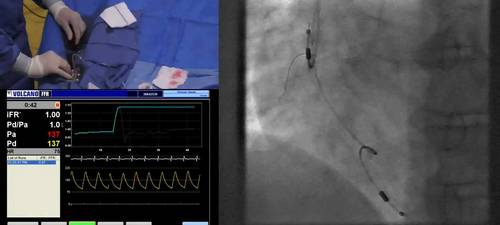

Examples of how to perform an iFR pullback assessment

A practical guide to performing the unique iFR pullback assessments.